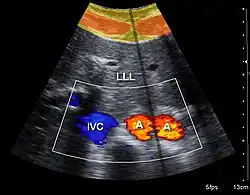

Doppler ultrasonography

Doppler ultrasonography employs the Doppler effect to assess whether structures (usually blood)[58][61] are moving towards or away from the probe, and their relative velocity. By calculating the frequency shift of a particular sample volume, flow in an artery or a jet of blood flow over a heart valve, its speed and direction can be determined and visualized, as an example. Color Doppler is the measurement of velocity by color scale. Color Doppler images are generally combined with gray scale (B-mode) images to display duplex ultrasonography images.[62] Uses include:

- Doppler echocardiography is the use of Doppler ultrasonography to examine the heart.[63] An echocardiogram can, within certain limits, produce accurate assessment of the direction of blood flow and the velocity of blood and cardiac tissue at any arbitrary point using the Doppler effect. Velocity measurements allow assessment of cardiac valve areas and function, abnormal communications between the left and right side of the heart, leaking of blood through the valves (valvular regurgitation), and calculation of the cardiac output and E/A ratio[64] (a measure of diastolic dysfunction). Contrast-enhanced ultrasound using gas-filled microbubble contrast media can be used to improve velocity or other flow-related measurements of interest.

Compression is used in this ultrasonograph to get closer to the abdominal aorta, making the superior mesenteric vein and the inferior vena cava look rather flat.